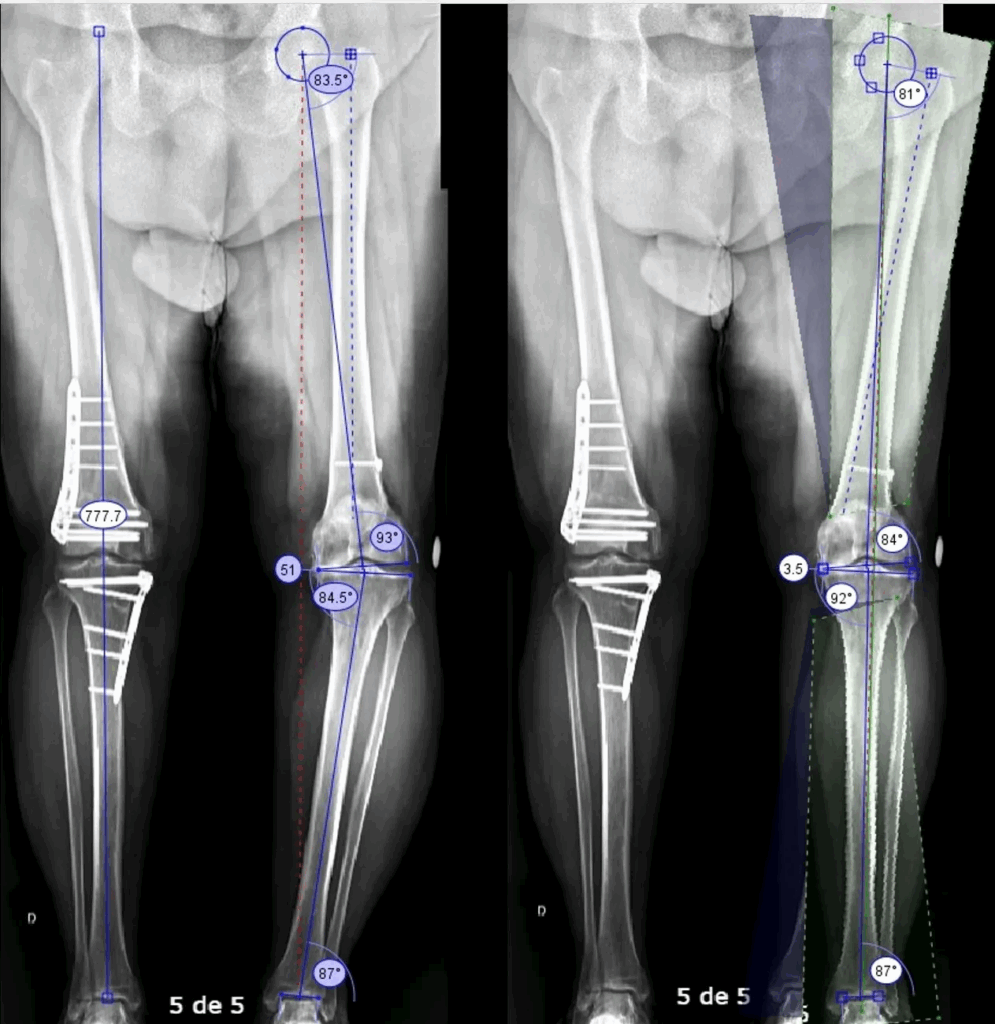

3. Articulação muito deformada

Quando existe desalinhamento importante, muitas vezes o correto é realizar cirurgia corretiva (osteotomia).